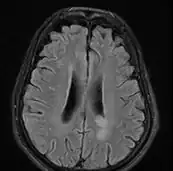

![]() ![]() text: From left to right: Cryptococcosis lung, cryptococcosis brain | |

MRI brain: cryptococcus